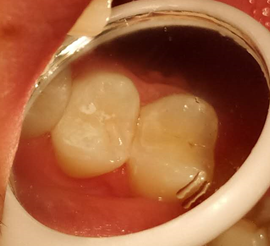

顾名思义,就是龋坏在相邻两颗牙齿之间,刚开始的时候从外面是基本看不出来的,可能只会出现吃东西时塞牙的症状。但如果通过专业检查配合拍X光片一般就能发现。

邻面龋主要是因为牙缝难以清洁,长期菌斑食物残留,牙齿邻接面被细菌侵蚀,慢慢缺损,因为位置比较隐蔽,不易发现,当发现的时候,缺损往往比较大了。